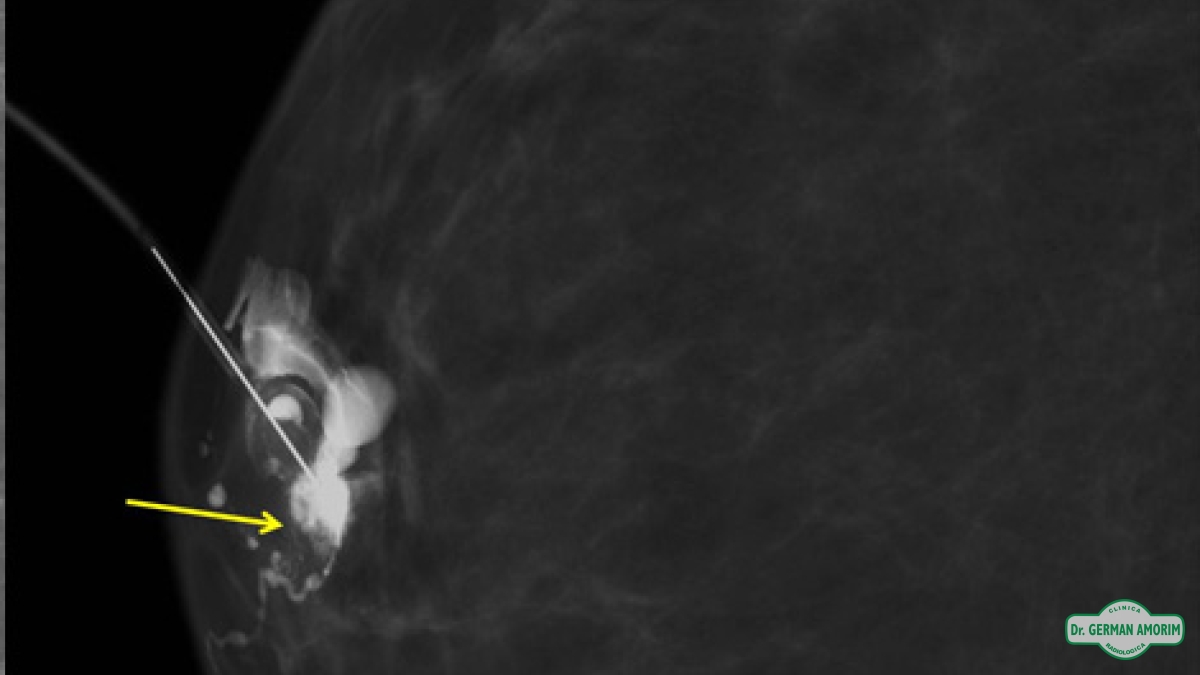

Galactografía

La galactografía es uno de los procedimientos intervencionistas de la mama que consiste en la realización de mamografías tras la administración de contraste radiopaco a través de un orificio en el pezón.

La lesión intraductal más frecuente es el papiloma y aunque el carcinoma intraductal tiene una frecuencia menor, al no poder distinguir entre ellas con este método de imagen, se recomienda la escisión quirúrgica. Es en este contexto que la galactografía sirve de mapa prequirúrgico para identificar correctamente el conducto patológico, la extensión de la lesión intraductal y la posible existencia de lesiones múltiples.

Entre las ventajas de esta técnica de imagen podemos mencionar la alta capacidad de definición de los ductos y de las posibles lesiones intraductales tras la administración de contraste, permitiendo así un mapa prequirúrgico para una escisión lo más selectiva posible.